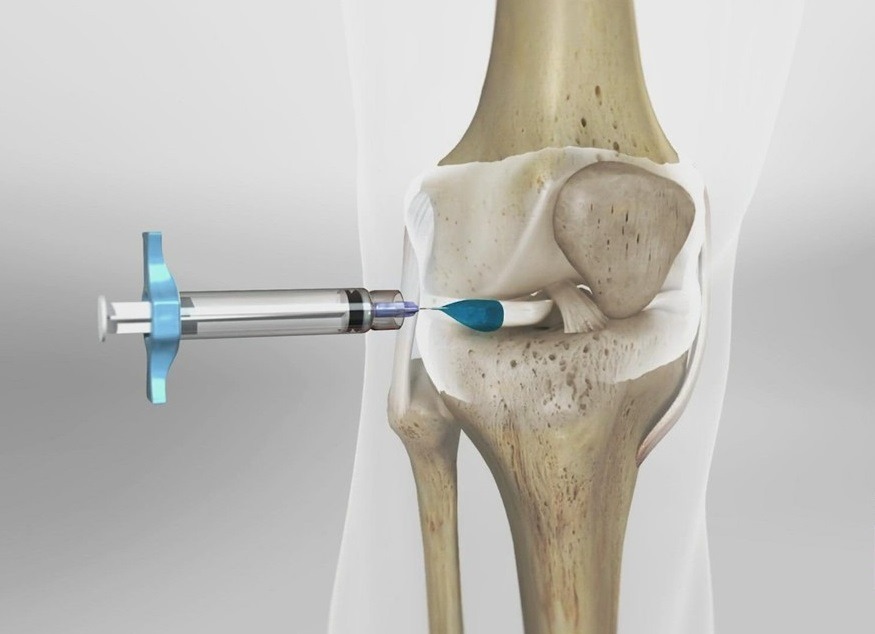

تزریق ژل:

ژل مفصلی یا هیالورونیک اسید، مادهای طبیعی است که در مفاصل سالم وجود دارد و نقش روانکنندگی و جذب شوک را دارد. با افزایش سن یا آسیب مفصل، مقدار این ماده کاهش مییابد و باعث درد و خشکی مفصل میشود.

تزریق ژل به مفاصل باعث بازگرداندن این روانکنندگی، کاهش اصطکاک و بهبود حرکت مفصل میشود. اثر آن معمولاً کوتاهمدت تا میانمدت است و برای کاهش درد و بهبود کیفیت زندگی بیمار کاربرد دارد.

- ژل بیشتر نقش کمک علائم و روانکنندگی مفصل دارد.

نظر پزشکان درباره جایگزینی تزریق به جای جراحی

با توجه به صحبت های ویدیو بالا ژل مفصلی، درست مانند یک بالشتک طبیعی بین استخوانها و مفاصل عمل میکند. وقتی تزریق میشود، اصطکاک بین استخوانها کاهش پیدا میکند و حرکت مفصل راحتتر میشود. این اثر باعث کاهش درد و بهبود عملکرد مفصل میشود، به ویژه در مراحل خفیف تا متوسط آسیب مفصل.

به زبان ساده، ژل همان چیزی است که مفصل را روان و نرم نگه میدارد و باعث میشود فرد بدون درد بیشتری حرکت کند، درست مثل بالشتکی که از برخورد دو سطح سخت جلوگیری میکند.